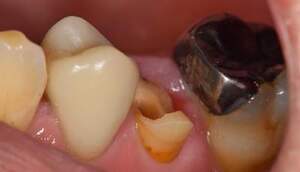

| 年齢 | 70代女性 |

|---|---|

| 主訴 | 前歯がとれた |

| 治療方針 | 長年使ってきた義歯の人工歯が磨耗し、臼歯部での咬合がすくなくなり、前歯部での接触が強くなったことで生じた前歯の破折なので、義歯も作り変える必要があります。 |

| 治療期間 | 8ヶ月 |

| 費用 | ・MTM 110,000円 ・ファイバーコア 16,500円 ・セラミッククラウン 110,000円 ・義歯 660,000円 |

※全て税込となります。

治療前で残存歯質がほとんどみられません。

残存歯質はないが、歯根は長いことを確認。

MTM治療開始時と終了後。右の根尖の透過像が実際に歯が動いた部分。

MTM中。頬側には審美面の回復のために仮歯がついています。

歯からはフック、隣り合った歯にはワイヤーが渡してあります。そこにゴムをひっかけて歯を挺出します。